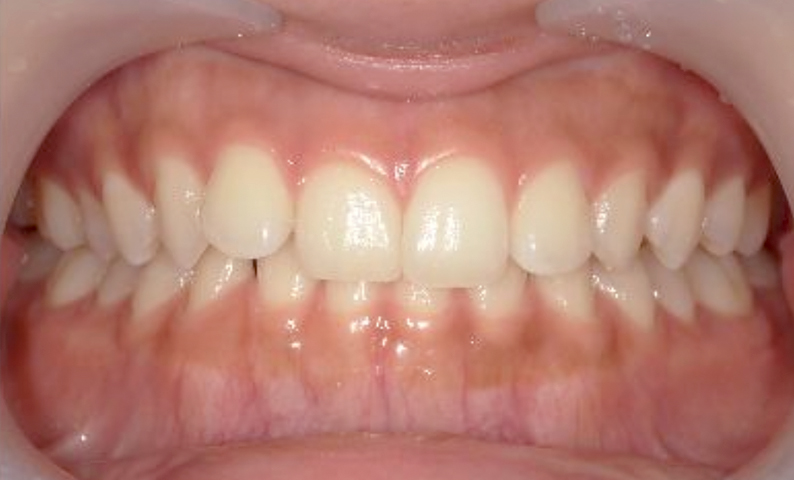

症例_001 前歯「捻転歯」症例

治療期間:6ヶ月金額:48万円+税20代女性少しのねじれ捻転歯下の八重歯

| Before | After |